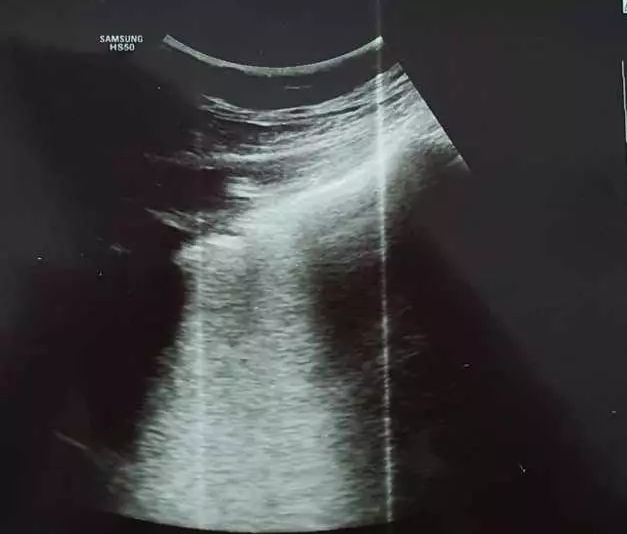

"Forme atipice de Covid-19. Toţi medicii care se confruntă cu patologia Covid-19 ar trebui să se gândească la această boală şi în cazul unui pacient cu simptome "ciudate" apărute în plină stare de sănătate! Unii mă vor întreba ce înţeleg prin simptome ciudate! Medicii înteleg ce spun! Astăzi am depistat un caz de Covid 19 la o pacientă relativ tânără, fără febră, fără tuse... fără niciun simptom considerat tipic sau sugestiv pentru Covid-19! Faptul ca am folosit ecografia pulmonară ce mi-a relevat modificări sugestive, m-a convins de necesitatea unui examen CT pulmonar. Examinarea tomografică a fost concludentă. Ulterior, a urmat şi confirmarea serologică. Simptomele pacientei erau doar astenie marcată, ameţeli, somnolenţă. Saturaţia in oxigen 98%! Fără comorbidităţi!", a scris medicul, pe contul personal, postând și mai multe fotografii cu plămânii pacientei.

"Imagine de ecografie pulmonară cu o bandă albă în spatele pleurei -Linii B confluente- sugestivă pentru inflamaţia alveolo-interstiţială", a explicat acesta.